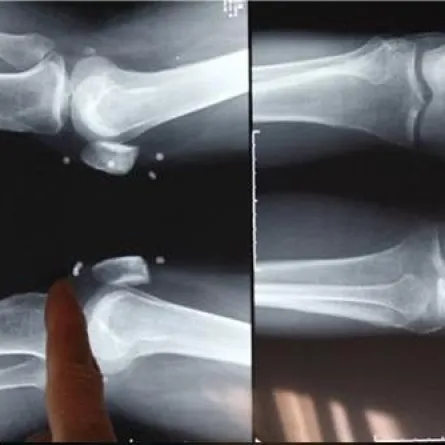

ونقلاً عن عدد من المواقع الإلكترونية، أوضح الرائد محمد الحمادي المتحدث الرسمي للدفاع المدني في منطقة الرياض أن غرفة عمليات الدفاع المدني بُلغت في تمام الساعة 20:29 من مساء اليوم الأربعاء بإصابة رأس طفلة تبلغ من العمر "8 سنوات" بسيخ حديدي سقط من عمارة مقابلة لمنزل ذويها في حي المغرزات، وانغرس في فروة رأسها.

وأضاف: على الفور تم تحريك الفِرق اللازمة، وتم التعامل مع الحالة وتحريرها من قِبل فِرق الدفاع المدني بقصّ السيخ، كما تم تسهيل تدخُّل فِرق الهلال الأحمر التي عملت على تقديم الإسعافات الأولية وإخراج السيخ من رأس الطفلة ونقلها إلى المستشفى للتأكد من سلامتها.